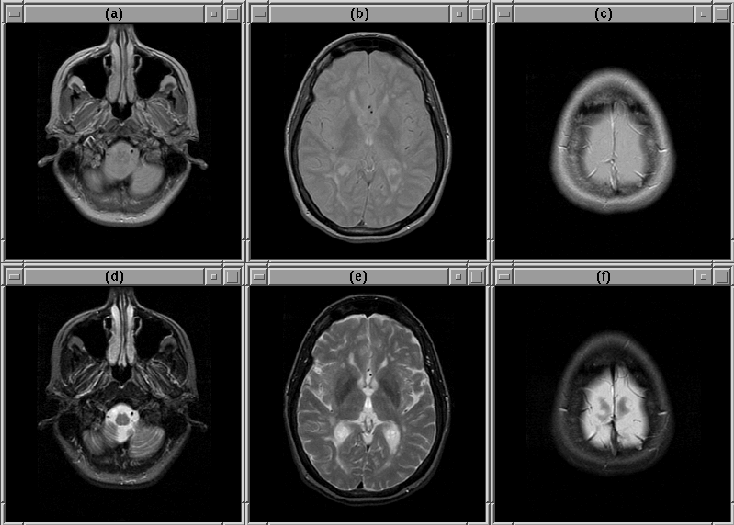

Selected slices for Data Set 2 are shown in Figure 8.2. Selected slices for Data Set 3 are shown in Figure 8.3. Notice that there is a region of bright voxels in slice 9, just above the brain, that might affect the detection of the intracranial boundary.

Figure 8.2: Selected slices from MRI Data Set 2. (Top) PD-weighted. (Bottom) T2-weighted. (a), (d) Slice 1. (b), (e) Slice 11. (c), (f) Slice 22.

Figure 8.3: Selected slices from MRI Data Set 3. (Top) PD-weighted. (Bottom) T2-weighted. (a), (d) Slice 1. (b), (e) Slice 9. (c), (f) Slice 22.